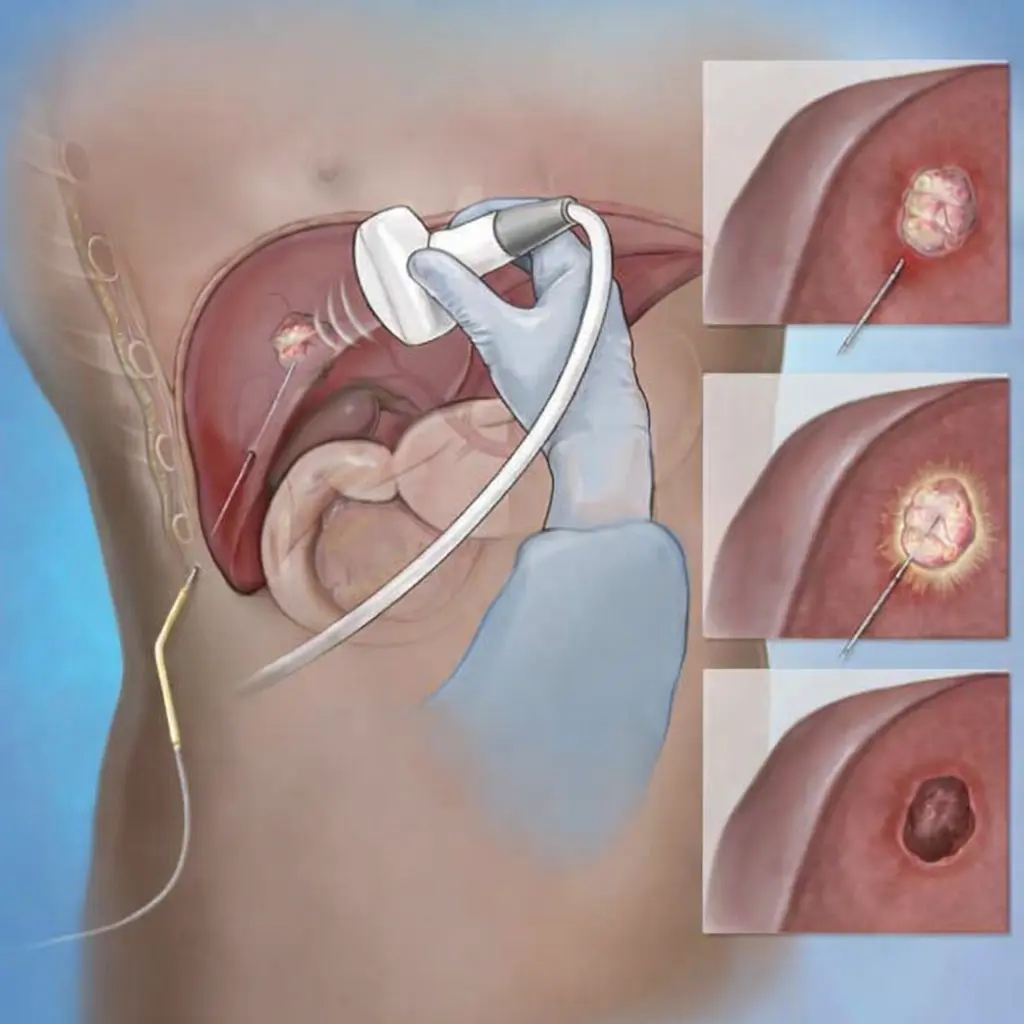

Image-guided cancer ablation is a minimally invasive, non-surgical treatment used to destroy selected cancers by precisely delivering heat energy directly into the tumour under real-time imaging guidance such as ultrasound or CT.

Instead of removing the tumour through open surgery, ablation targets and destroys cancer cells from within, while preserving surrounding healthy tissue and organ function.

Image-guided cancer ablation is performed through a tiny skin puncture, without any surgical incision.

- Anesthesia: Local anesthesia with sedation or general anesthesia (depending on tumour location)

- Procedure time: Typically 30–120 minutes